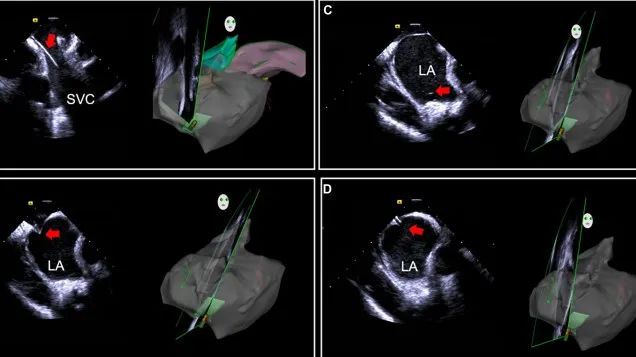

一種與心導(dǎo)管檢查相結(jié)合的超聲心動(dòng)圖診斷新興技術(shù),通過將超聲探頭置于心腔內(nèi)部,發(fā)射并接收超聲信號(hào),來(lái)精確獲取心臟解剖結(jié)構(gòu)、心臟血流動(dòng)力學(xué)等信息的實(shí)時(shí)成像。與其他影像技術(shù)相比,ICE技術(shù)具有操作簡(jiǎn)單、無(wú)輻射、安全性高、手術(shù)效率高、實(shí)用等優(yōu)勢(shì),ICE在很大程度上有望取代經(jīng)食道超聲心動(dòng)圖(TEE),成為電生理和結(jié)構(gòu)性心臟病領(lǐng)域的理想成像方式。

目前ICE技術(shù)已被應(yīng)用于左心耳封堵、房顫射頻消融、二尖瓣成形、房間隔缺損封堵等多種心臟介入手術(shù),應(yīng)用場(chǎng)景主要圍繞臟電生理、結(jié)構(gòu)性心臟病等領(lǐng)域,目前以電生理應(yīng)用為主。數(shù)據(jù)顯示,我國(guó)結(jié)構(gòu)性心臟病介入器械市場(chǎng)規(guī)模已從2017年的4億元增長(zhǎng)至2021年的20億元,年復(fù)合增長(zhǎng)率達(dá)48.3%;預(yù)計(jì)到2025年,該市場(chǎng)規(guī)模將達(dá)到104億元,可以預(yù)見ICE市場(chǎng)規(guī)模也將同步高速增長(zhǎng),未來(lái)市場(chǎng)發(fā)展空間廣闊。

心腔內(nèi)超聲(ICE)技術(shù)壁壘極高,國(guó)內(nèi)主要廠商核心部件仍舊為進(jìn)口,集成了超聲和圖像處理最前端技術(shù),包括超聲探頭、線纜、軟件成像算法等,是當(dāng)前內(nèi)窺超聲方向最具挑戰(zhàn)的領(lǐng)域。ICE的應(yīng)用經(jīng)歷了2D平面成像、3D三維立體成像、以及4D的實(shí)時(shí)三維立體成像階段。